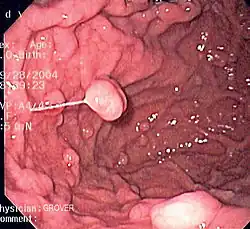

A series of radiographs can be used to examine the stomach for various disorders. This will often include the use of a barium swallow. Another method of examination of the stomach, is the use of an endoscope. A gastric emptying study is considered the gold standard to assess the gastric emptying rate.[50]

A large number of studies have indicated that most cases of peptic ulcers, and gastritis, in humans are caused by Helicobacter pylori infection, and an association has been seen with the development of stomach cancer.[51]